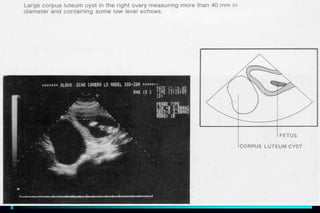

 Gynecology : - Uterus, Ovaries, Adnexa

- Pelvic mass reveals mass or

enlargement of pelvic organ

1. Determine the size and location of lesions

2. Characteristics of the lesion: cystic, complex or

solid